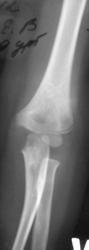

Вывих локтевой с эпифизеолизом локтевой и лучевой?

Не работаю с детьми, поэтому вопрос: почему вывих локтевой? Вроде всё на месте. Эпифизеолиз согласен, только лучевой.

Остео-эпифизеолиз плеча (головчатого возвышения) без смещения

Рассмотрел «поближе». Похоже, все-таки ошибся, перелом плеча есть.